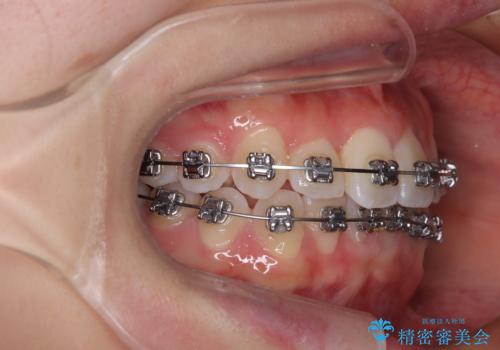

前歯のクロスバイト 裏側に隠れた歯をワイヤー装置で短期間治療

- 矯正装置

- メタルブラケット

- 上顎前歯のクロスバイトを気にして来院された患者様です。

ワイヤー矯正でもマウスピース矯正でも対応可能でしたが、マウスピースによる自己管理に一切の自信がないとのことで、ワイヤー装置にて矯正治療を行うこととしました。

装置の外見を気にしていましたが、短期間で治療を終えることができるだろうと伝えると、安価であるメタルブラケットを選択されました。

想定通り、1年強で綺麗に仕上げることができました。